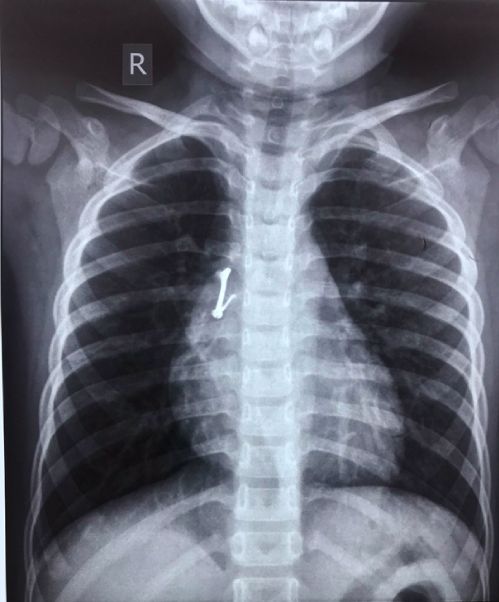

Khi nội soi tiếp cận chiếc móc khóa đang nằm trong phổi bé trai 5 tuổi, các bác sĩ phát hiện phần móc nhọn đâm thủng đường thở, xâm lấn mạch máu tim.

Nằm trong đường thở lâu ngày, chiếc móc khóa bằng kim loại đã ăn chắc vào mô phổi của bé, gây viêm các mô xung quanh, có dấu hiệu hoại tử, chảy máu. Phẫu thuật viên nghi ngờ dị vật đã làm thủng đường thở, xâm lấn vào mạch máu ở vùng trung thất tim.

"Nếu cố dùng kìm để gắp dị vật có thể gây vỡ mạch máu, thủng tim hoặc tràn khí ép tim, ngừng tim, bé có thể chết ngay trên bàn mổ", bác sĩ Nguyễn Tuấn Như, Trưởng khoa Tai mũi họng Bệnh viện Nhi đồng 1 cho biết, ngày 23/4.

Ca mổ nội soi buộc phải dừng lại. Trong khi bé vẫn nằm trên bàn mổ nội soi, các bác sĩ nhanh chóng hội chẩn cấp cao, quyết định chuyển sang mổ mở lồng ngực kết hợp nội soi gắp dị vật.

Các bác sĩ chọn phương án vừa mổ hở lồng ngực vừa nội soi lấy dị vật, dự trù xảy ra tình huống dị vật gây xuất huyết hoặc ngừng tim, kíp mổ vẫn có thể can thiệp cầm máu, hồi sức tim kịp thời, bệnh nhi có cơ hội sống.

Bác sĩ Đào Trung Hiếu, Phó giám đốc Bệnh viện Nhi đồng 1, cho biết bệnh nhi hồi phục sức khỏe tốt.